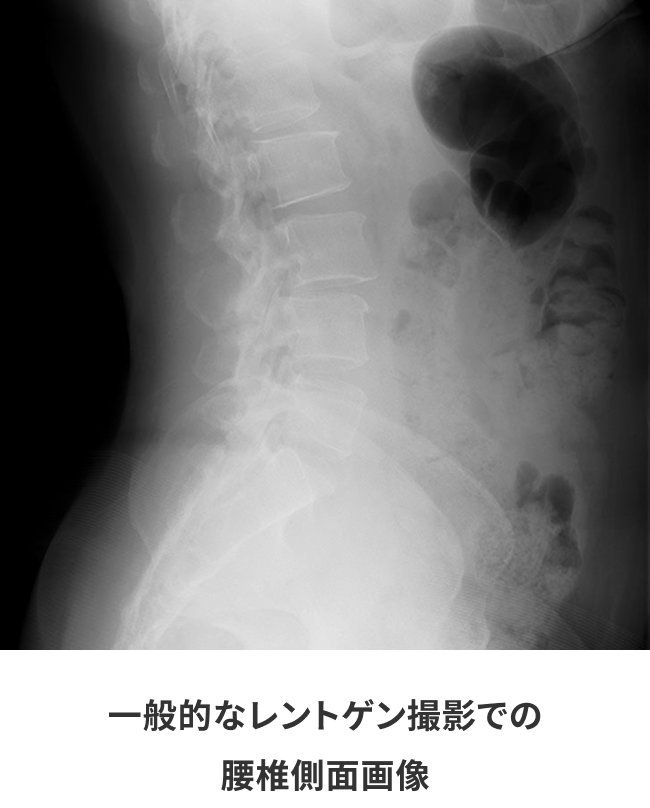

同一患者における一般撮影とキヤノンのデジタルX線TVシステムとの画像比較

検査室に以前設置されていたX線TVシステムでは、画質を求めると線量を上げなくてはならず被ばく量が増えてしまうため、線量をおさえると細かいところまで確認ができないという悩みを抱えていました。

17インチx17インチのデジタルX線検出パネルと新開発の画像処理装置といった、これまでキヤノンが培ってきた技術の組み合わせによって透視画像のノイズ低減とコントラスト分解能が向上し、高画質化を実現しながら従来機種と比べ線量低減を実現しています。